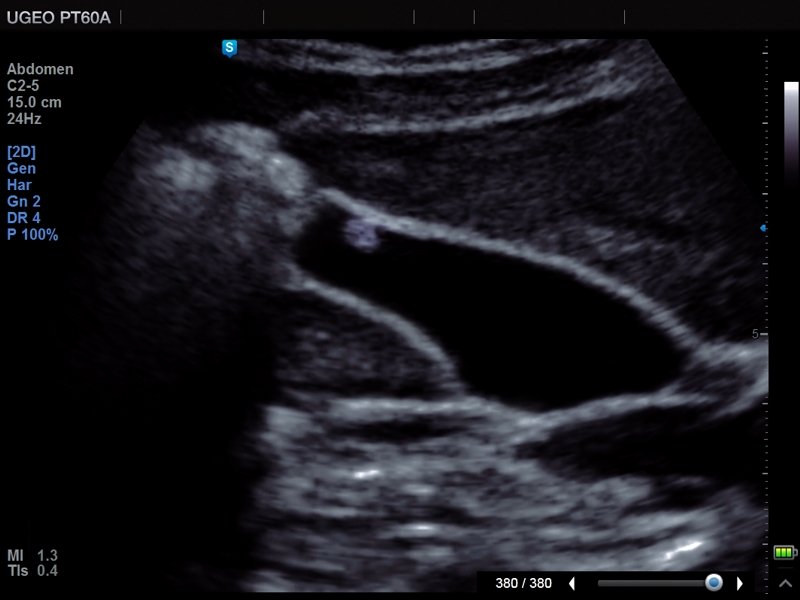

Gall bladder - polyp, В-mode (echogramm №678)

[RU] Ultrasound image №678: Gallbladder polyp (zoom) in В-mode.

Echogramm was received by ultrasound scanner PT60 (out of production).